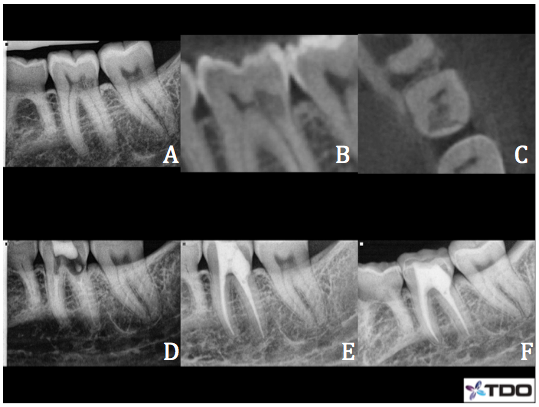

Case 5– #19 Class II ECIR with internal repair

44 y/o female presented for the evaluation of #19 due to a Class II ECIR lesion that was discovered on a routine bitewing. Patient was asymptomatic. The tooth was vital and testing WNL to cold. Apical tissues appeared WNL. CBCT sagittal slice (B) showed the ECIR lesion is limited to the coronal tooth structure and appears to communicate with the pulp chamber. Axial slice (C) showed small, pinpoint root surface perforations on the DL and DB line angles.The pulp tissue was extirpated and pulpectomy was completed. NaOCl/EDTA/CHX irrigation. Ca(OH)2 was packed to the apices. Each canal was covered with a small cotton pellet and Opaldam. I then excavated the ECIR lesion and the area was soaked with 90% trichloracetic acid. I then patched the perforations with Geristore (D) and temporized with cotton and cavit. Patient returned after a couple of weeks and remained asymptomatic. Endodontic treatment was completed and I restored the defect and completed the buildup with Geristore (E). The patient was referred back to her general dentist for the crown. Patient remained asymptomatic at her 6 month recall (F) and crown had been placed.